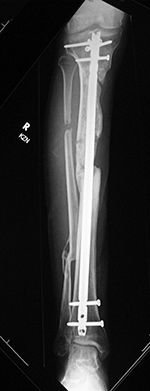

Intramedullary tibial nail and fibula Rush rod

Right tibia fracture dynamization

Right tibia dynamization - before

Right tibia dynamization - after

43 year-old man with complex, healing right tibia and fibular fractures. There is an intramedullary rod (nail) in the right tibia. Four locking screws are present proximally and two distally. After dynamization the distal locking screws have been removed.